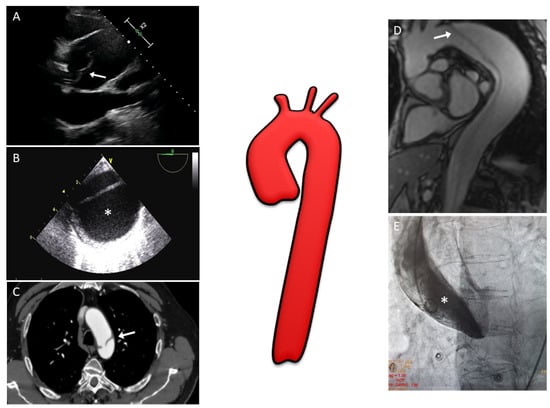

Figure 1.

Multimodality imaging assessment of aortic dissection: (A) Two-dimensional transthoracic echocardiography showing a linear echo of an intimal flap (arrow) in a dilated aortic root above aortic valve level; (B) Two-dimensional transesophageal echocardiography in patients with aortic dissection involving the entire aorta; the false lumen (*) is typically larger and often compresses the true lumen, potentially affecting distal aortic flow; (C) CT image with evidence of the intimal tear (arrow) at the level of the aortic arch; (D) MRI with SSFP imaging in the oblique sagittal plane showing an intimal flap (arrow) from the aortic arch to abdominal aorta; (E) Aortic angiography performed in a patient with suspected inferior ST-segment elevation myocardial infarction revealing a type A aortic dissection (one may note that the pigtail catheter is located in the false lumen (*) of the dissection). CT, computed tomography; MRI, magnetic resonance imaging; SSFP, steady-state free precession.